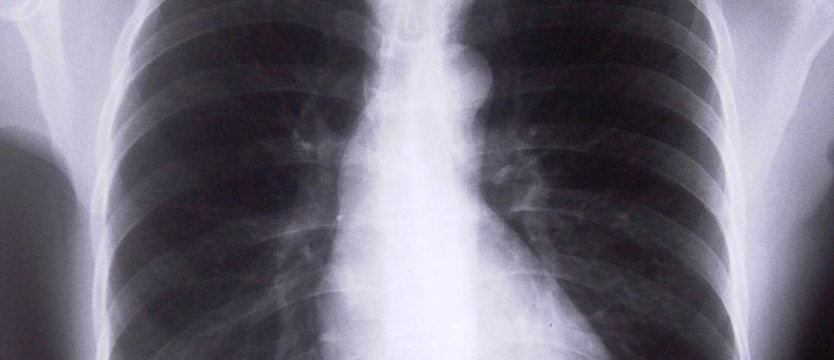

Nadciśnienie płucne (NP) jest rzadką, szybko postępującą, śmiertelnie niebezpieczną chorobą, która atakuje płuca i serce. NP to zespół objawów klinicznych spowodowanych wzrostem ciśnienia w krążeniu płucnym, czyli w obiegu krwi pomiędzy prawą komorą, płucami a lewym przedsionkiem serca. Istnieje kilka kategorii tej choroby, np. spowodowane wrodzoną wadą serca, czy występujące w przebiegu chorób płuc. Przewlekłe zakrzepowo-zatorowe nadciśnienie płucne oraz tętnicze nadciśnienie płucne są najgroźniejsze.